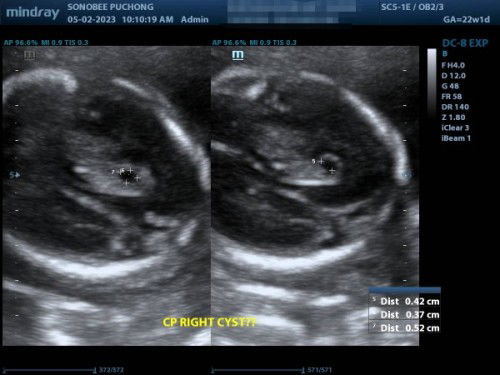

Hai assalamualaikum ibu2 semua, nak minta pendapat, last week sy ada buat details scan. Then waktu scan, sonographer tu inform possibilities ada cyst di bahagian kepala baby belah kanan (macam dlm gambar). Sonographer tu minta repeat scan 4minggu lagi sebab dia pun tak pasti. Nak tanya, ada tak ibu2 yg ada pengalaman macam ni? Tadi dh refer nurse di KK, dia kata maybe sebab hormon tp nurse cakap better pergi repeat sekali lagi & dapatkan surat dri Sono if betul. Mohon ibu2 doakan baby sy tiada apa yg pelik, yg lain2 semua okay, alhamdulillah, cuma yg 1 ni je sonographer tak boleh bagi kata putus.